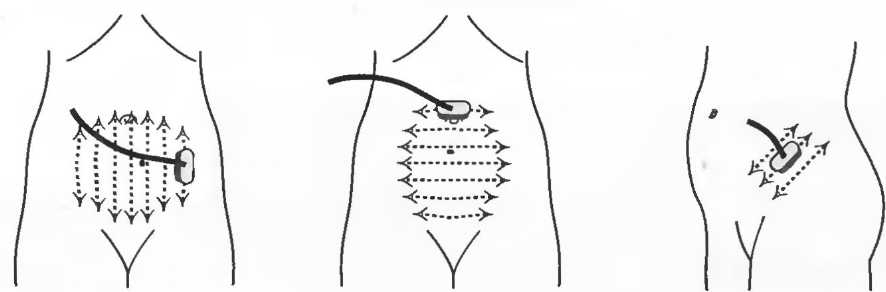

Подготовка

1. Подготовка